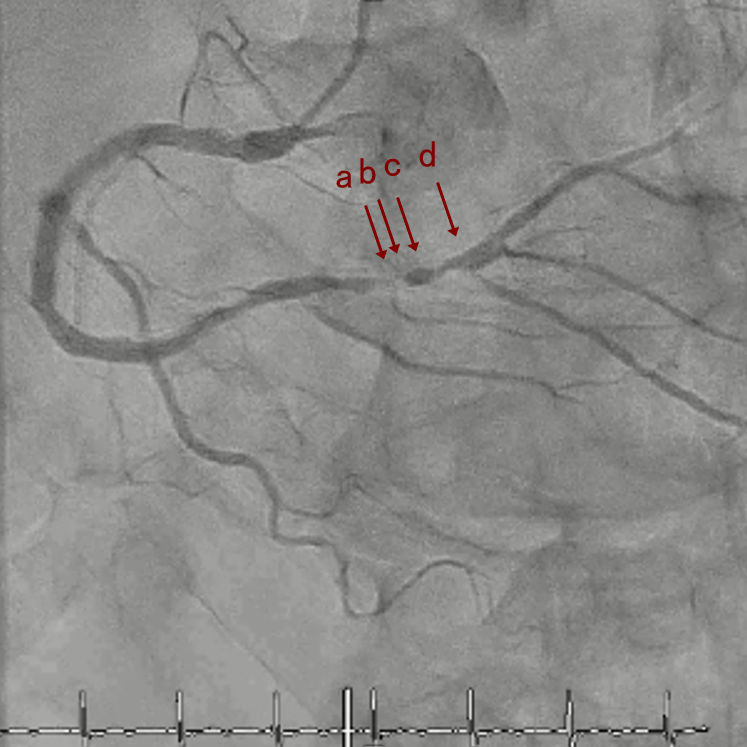

CAG

RCA distalの高度石灰化狭窄病変

IVUS imaging

IVUSでは8時方向からPD枝がはいいてくる。

PreのIVUSではaの部位のみlipid plaqueを認め削ることでdistal embolismのリスクがあり、そのほかは270度の偏心性石灰化であるがwire biasは良好。

OAS low speedによる引きを赤線の区間行う方針とした。